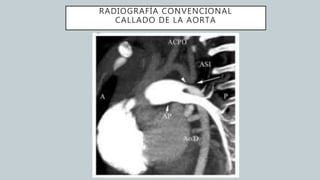

El documento detalla la anatomía del corazón y su ubicación en la caja torácica, incluyendo estructuras como las aurículas, ventrículos y arterias. También se abordan técnicas de diagnóstico por imagen, como radiografías y TAC, para visualizar la morfología cardíaca. La información está dirigida a estudiantes de medicina y profesionales interesados en la anatomía cardíaca.